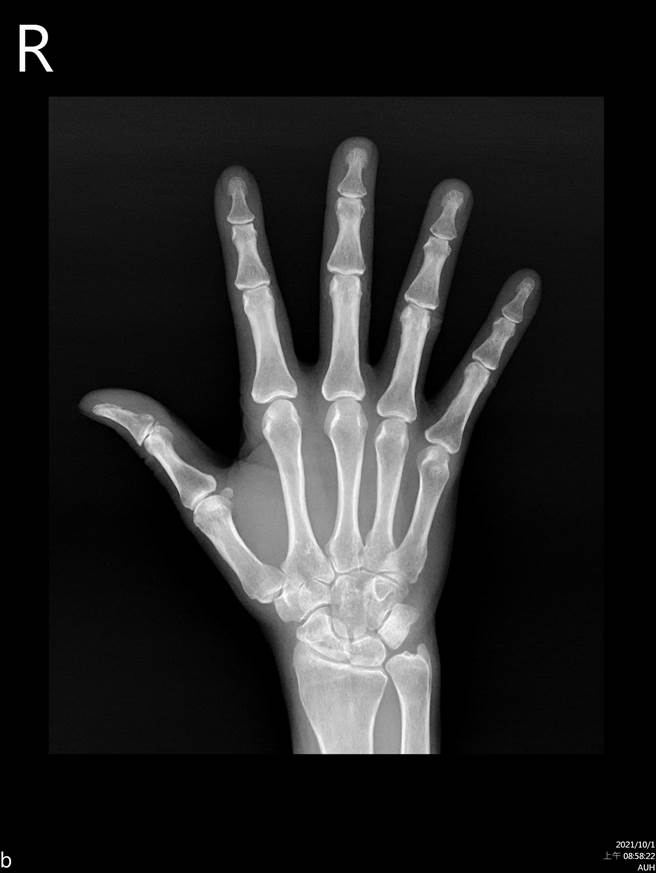

亞洲大學附屬醫院過敏風濕免疫科主治醫師陳俊宏指出,類風濕性關節炎是國人常見的慢性關節疾病,其屬於全身性自體免疫疾病,通常好發於女性,若幼年發病又未獲得適當治療,則可能造成殘疾、進而失去生活自理能力。目前醫界認為其與基因、環境有關。

陳俊宏表示,此疾病患者因免疫系統失調,會攻擊自己的關節,造成關節發炎、變形,嚴重者甚至會導致內臟器官發炎、危及生命。目前治療方式包括使用消炎止痛藥、類固醇及免疫製劑,若經治療半年仍效果不佳,則可考慮第二線的單株抗體、生物製劑或小分子生物製劑治療。